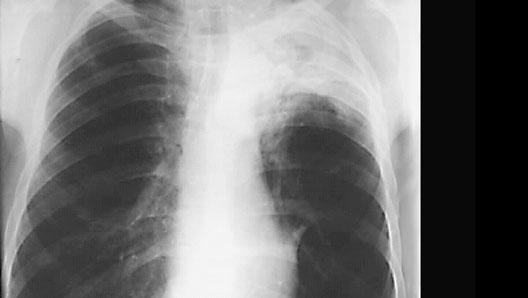

Lung Cancer

Roll mouse over image to display labels.